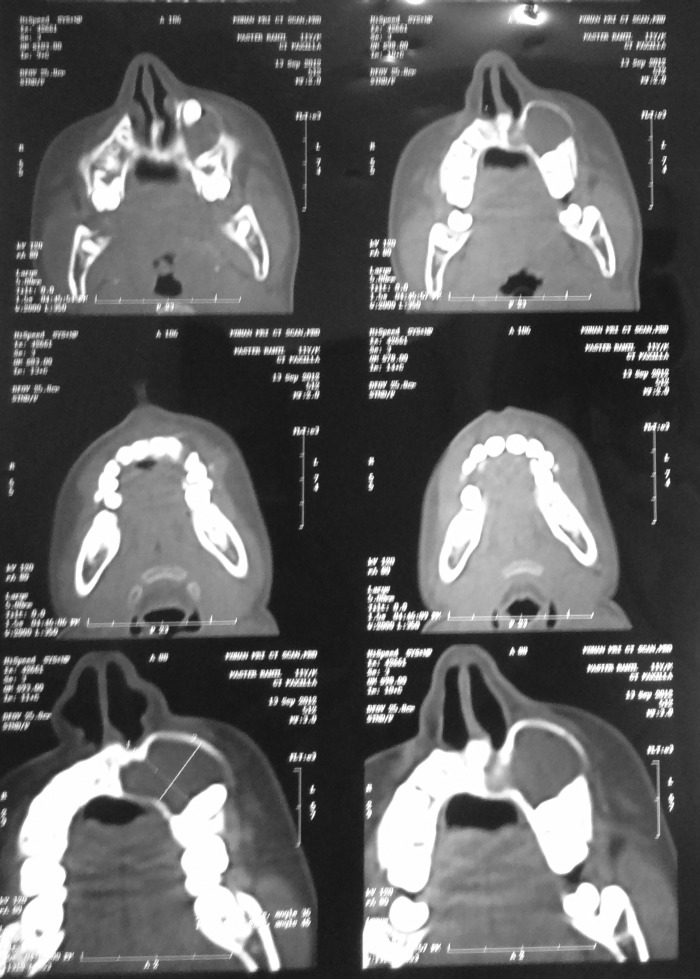

In order to determine the exact location of the canine tooth, maxillary occlusal radiograph and CT was performed with paranasal inspection. In the axial cross section, a radio-opaque image of the tooth and a radiolucent image of the cyst attached to the tooth were seen. Based on clinical and radiological examination, a provisional diagnosis of dentigerous cyst was made (figure 3).

Figure 3.

CT showing the extent and borders of the keratocystic odontogenic tumour.

The occurrence of KCOT in maxilla is relatively rare and more uncommon is its occurence in a 11-year-old child with invasion of the maxillary sinus that is again unusual, which was seen in this case. In the CT scan, the lesion appeared to be a large, well-defined, expansile, thin-walled cystic lesion extending cranially into the maxillary sinus.